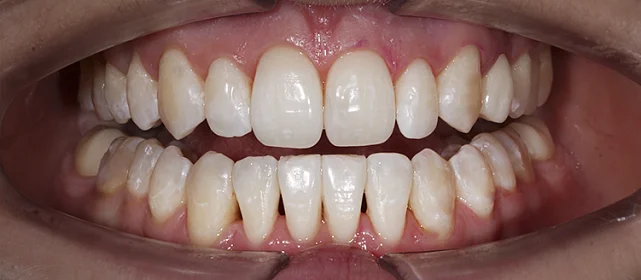

Установка ретейнеров на нижнюю и верхнюю челюсть

Фотографии опубликованы с согласия пациента

Дьячкова Инна Владимировна

Стоматолог - ортодонт

Стаж более 11 лет